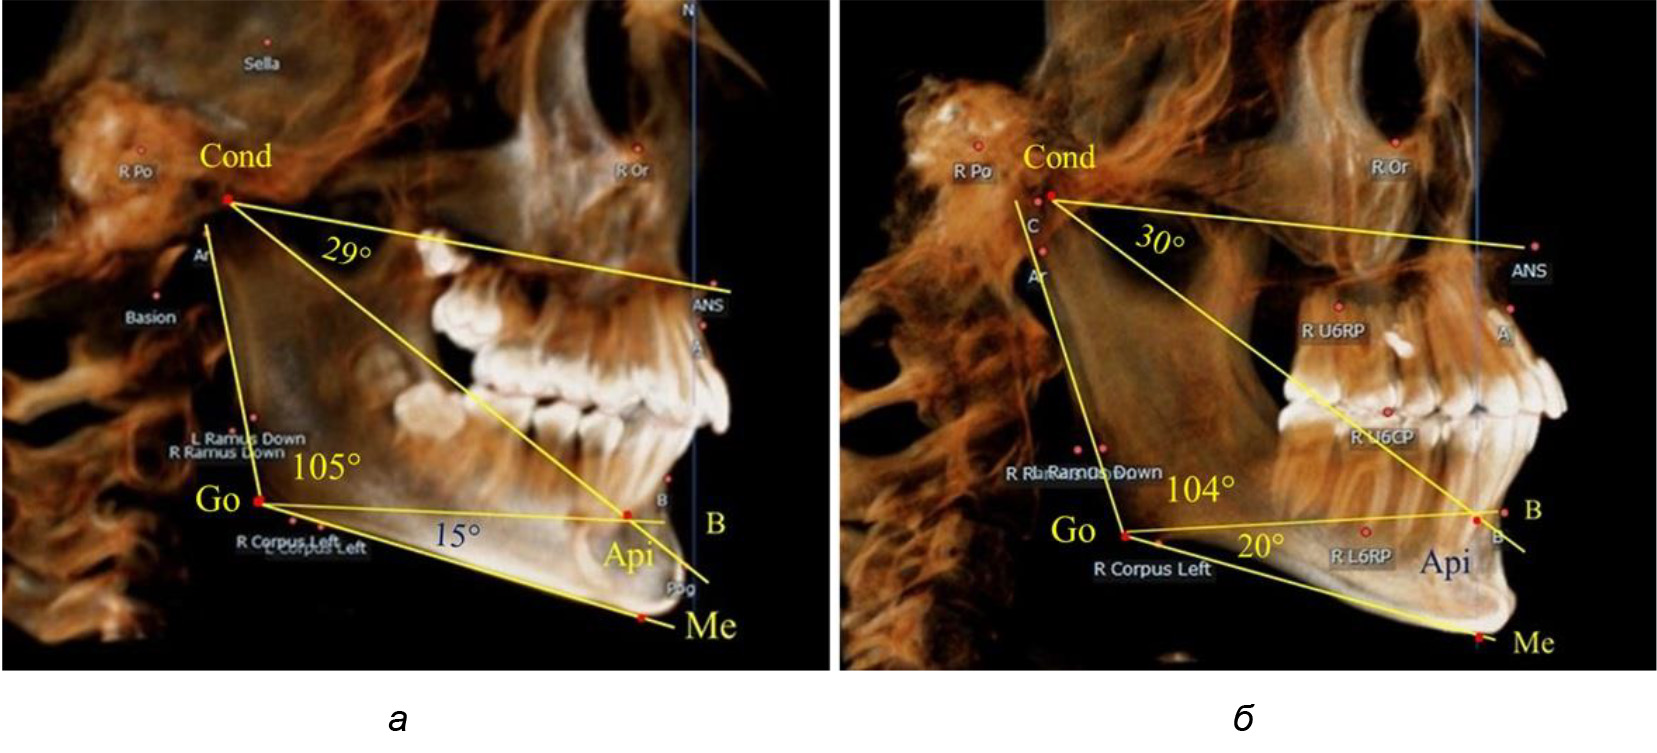

При анализе 16 рентгенограмм с аномалиями окклюзии в вертикальном направлении были выявлены признаки изменения основного гнатического угла. Так, для гнатических аномалий глубокой резцовой окклюзии/дизокклюзии (9 человек) отмечалось уменьшение угла гнатической части лица, величина которого была менее 26°. В то же время для гнатических аномалий (7 человек) вертикальной резцовой дизокклюзии («открытый» прикус) определялось увеличение угла гнатической части лица, который превышал значения в 33° (рис. 7).

Рис. 7. Варианты ТРГ при глубоком прикусе (а) и при открытом прикусе (б)

На представленных клинических примерах, несмотря на различия параметров основного угла гнатической части лица, определялись однотипные варианты угла нижней челюсти Ar-Go-Me и его составных частей Ar-Go-Api и Api-Go-Me.

Таким образом, установлено, что основным показателем, определяющим оптимальные параметры гнатического отдела лица, является угол гнатического отдела лица, образованный пересечением линии, соединяющей точку передней носовой ости с верхней точкой суставной головки SNA-Cond, и линией, отходящей от суставной точки до верхушки корня нижнего медиального резца Cond-Api. Средняя величина угла гнатического отдела SNA-Cond-Api составляла (29,96 ± 0,84)° при физиологической окклюзии постоянных зубов и практически была аналогичной во все периоды онтогенеза.